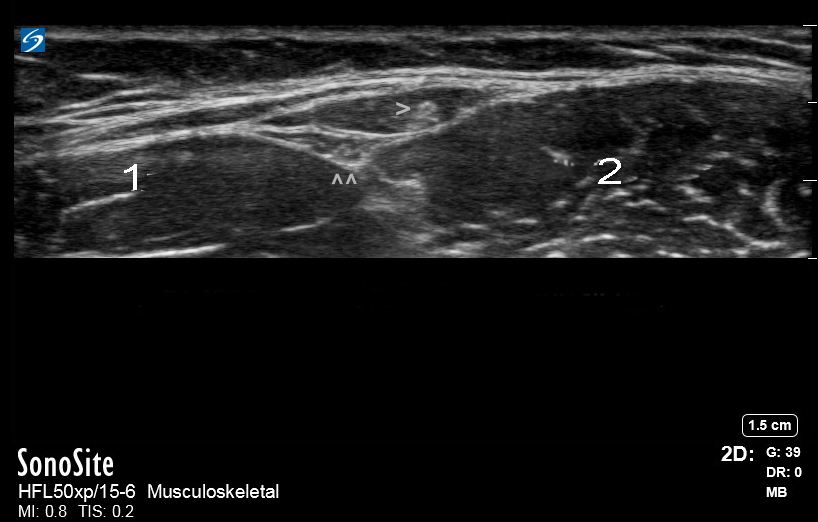

髋关节外侧股皮神经图像

缝匠肌

股直肌